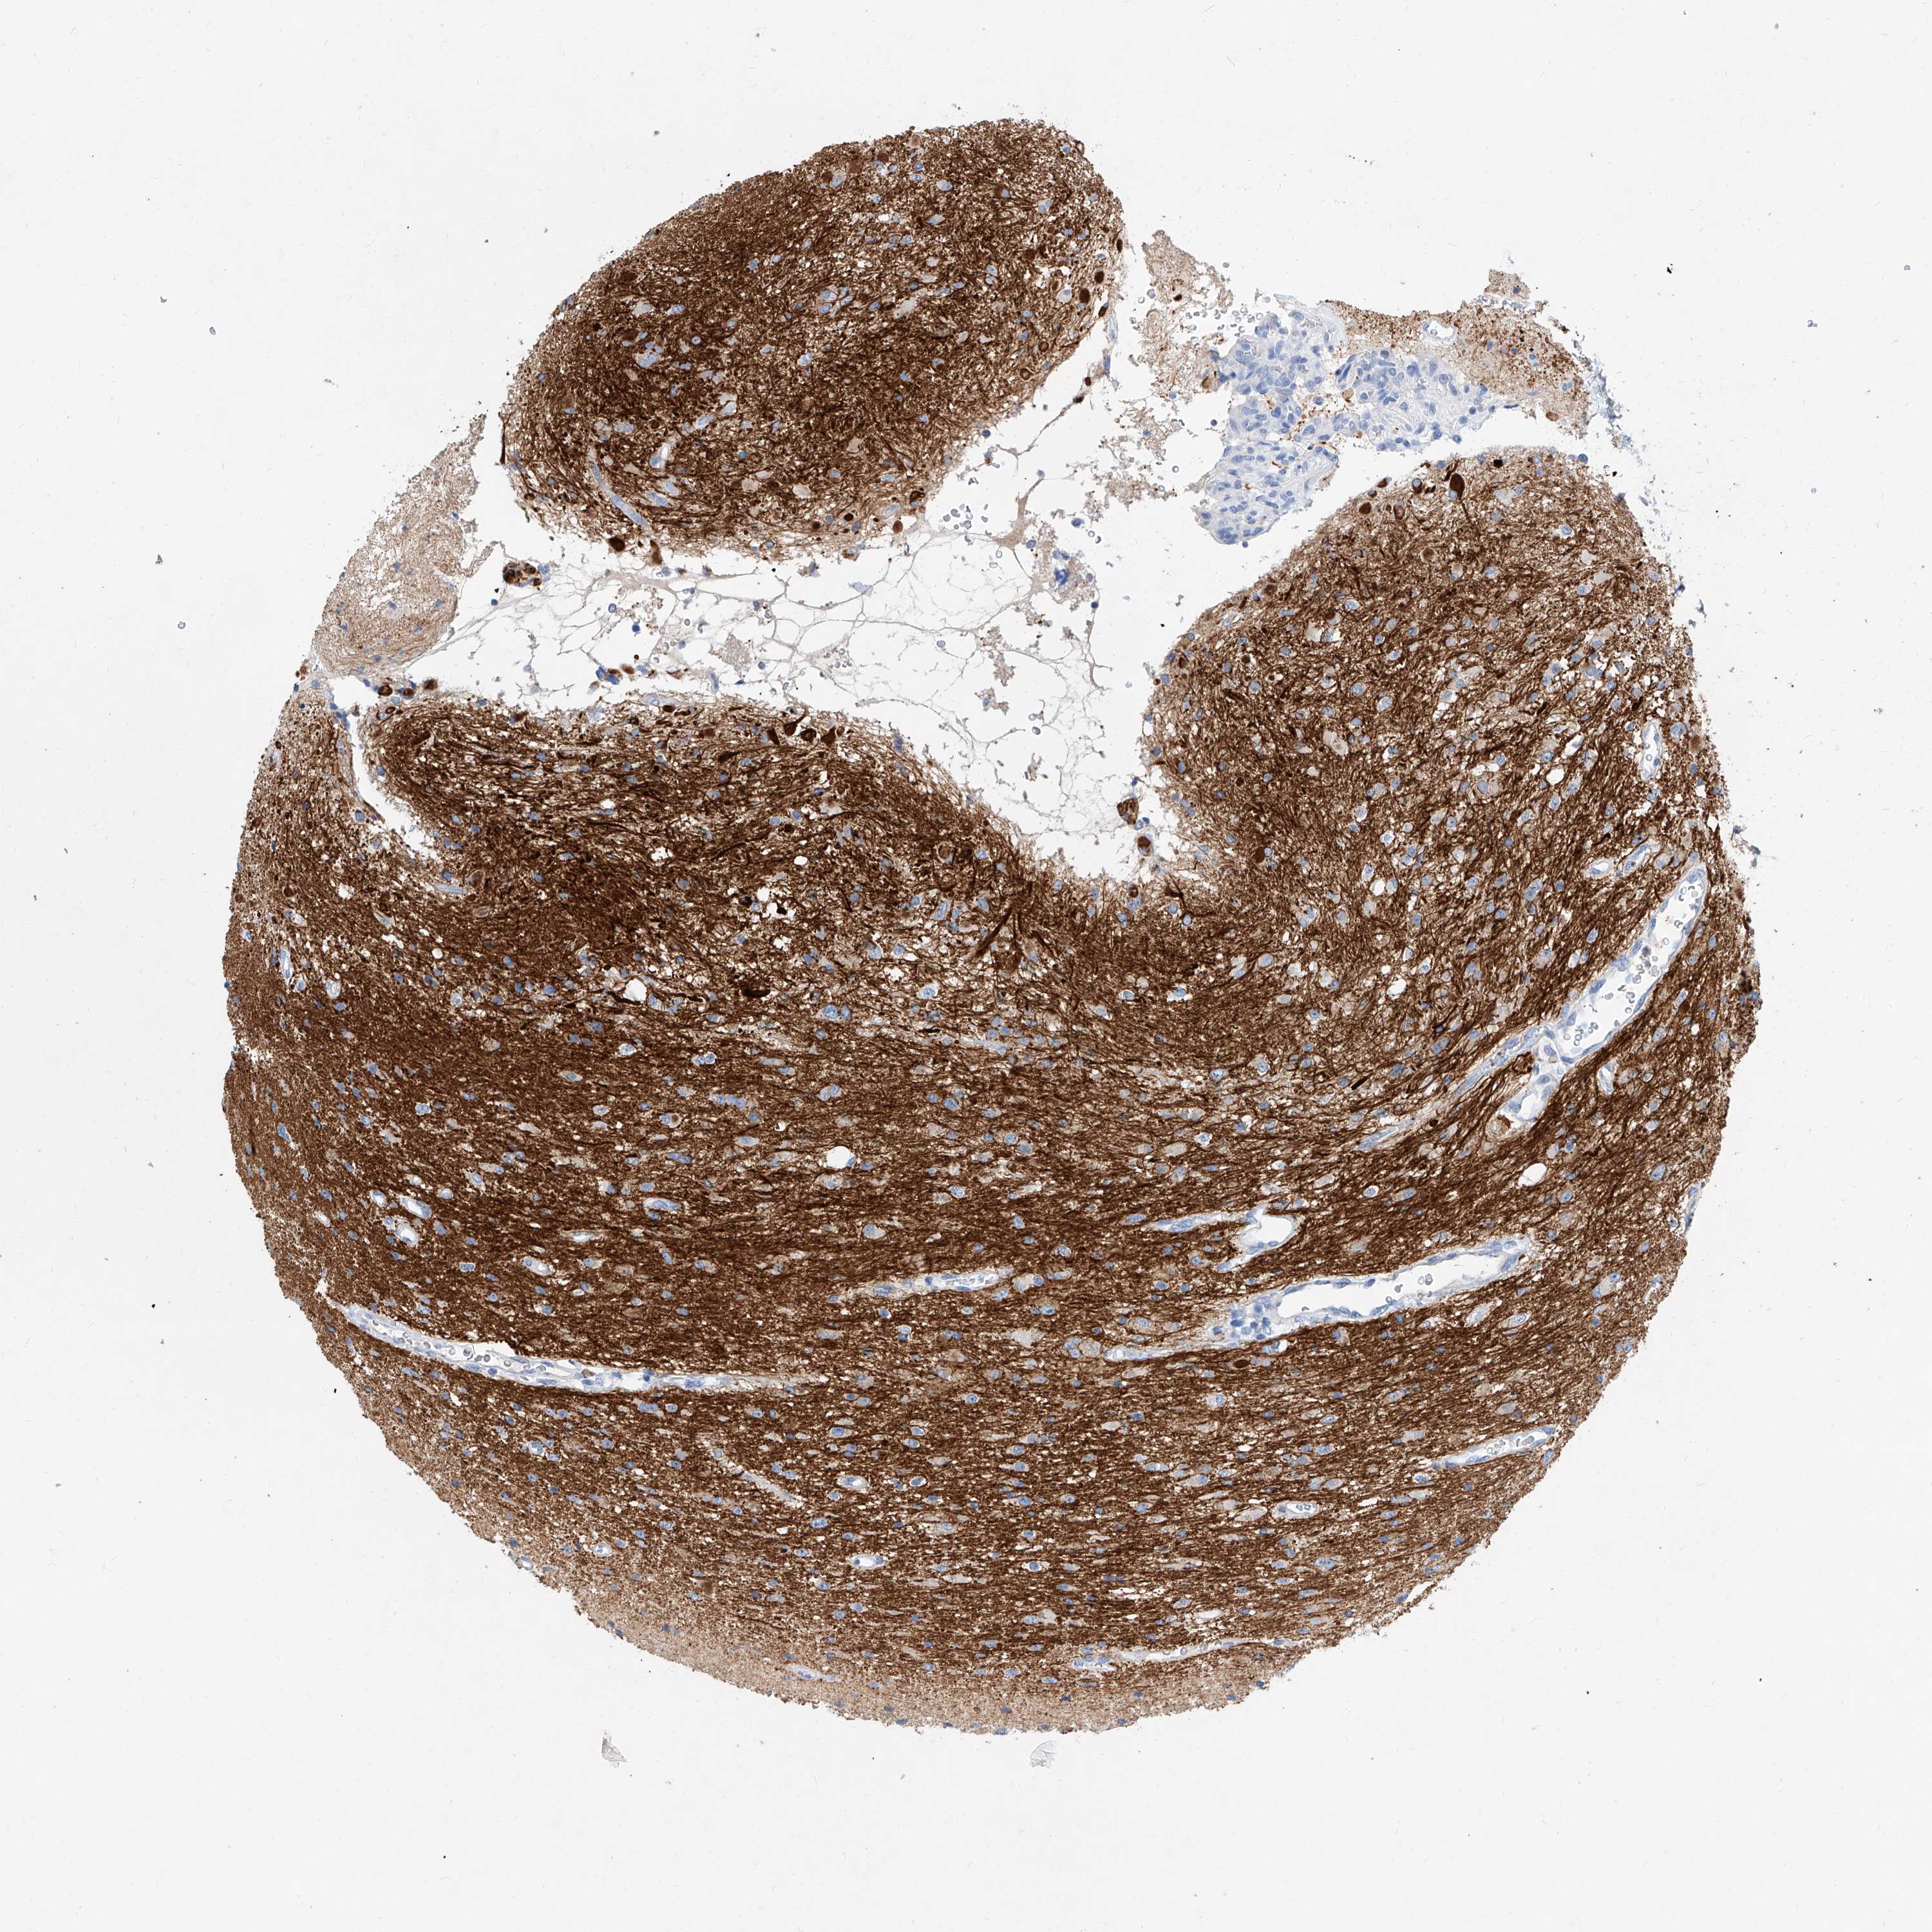

GLIOMA - Protein expressioni

A mouse-over function shows sample information and annotation data. Click on an image to view it in a full screen mode. Samples can be filtered based on level of antibody staining by selecting one or several of the following categories: high, medium, low and not detected. The assay and annotation is described here.

Note that samples used for immunohistochemistry by the Human Protein Atlas do not correspond to samples in the TCGA dataset.

Antibody stainingi

Antibody staining in the annotated cell types in the current human tissue is reported as not detected, low, medium, or high, based on conventional immunohistochemistry profiling in selected tissues. This score is based on the combination of the staining intensity and fraction of stained cells.

Each image is clickable and will lead to virtual microscopy that enables deeper exploration of all samples and also displays staining intensity scores, fraction scores and subcellular localization as well as patient and tissue information for each sample.

Antibody HPA030781

Staining

High

Medium

Low

Not detected

Intensity

Strong

Moderate

Weak

Negative

Quantity

>75%

75%-25%

<25%

None

Location

Nuclear

Cytoplasmic/membranous

Cytoplasmic/membranous,nuclear

Glioma, malignant, High grade

Glioma, malignant, Low grade

Glioblastoma, NOS